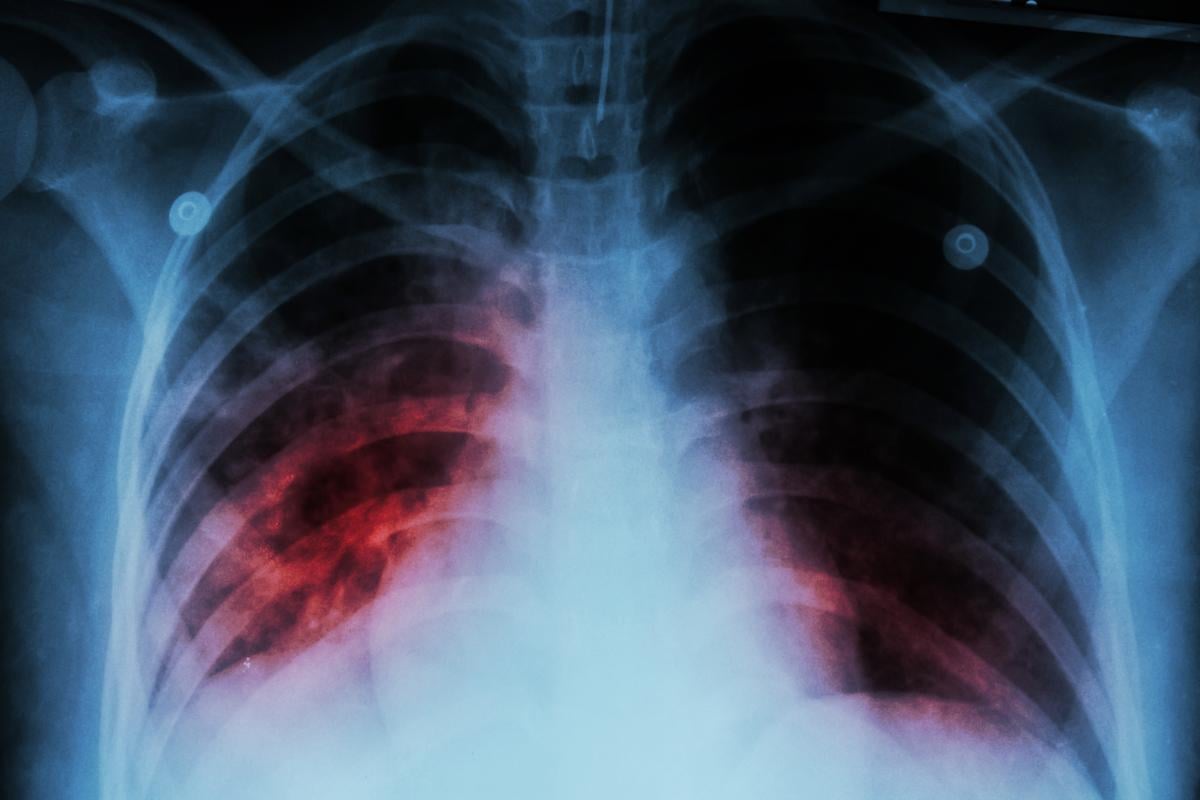

Adobe Stock

Tuberculosis is caused by airborne bacteria that mostly attacks the lungs. Roughly a quarter of the global population is estimated to have TB, but only about 5% to 10% of those develop symptoms, the WHO said.